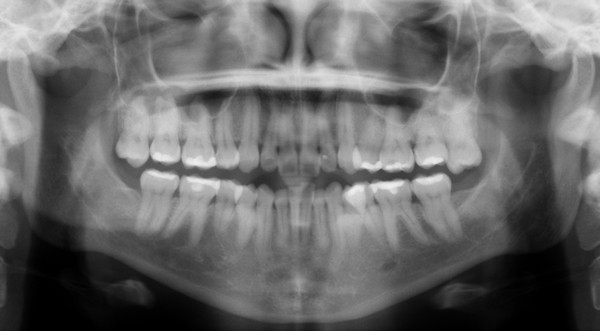

Radiografía panorámica